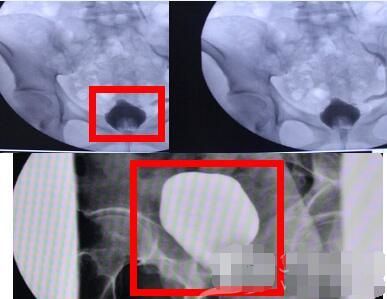

这5%的原型细结晶体粉状,不仅一路刮伤输尿管内壁,更会导致膀胱炎、膀胱挛缩,严重时可以致使膀胱挛缩至正常人的十分之一(所以无法储存像正常人一样储存过多尿液,导致尿频、尿急),这在医学上叫典型的氯胺酮相关性膀胱炎。